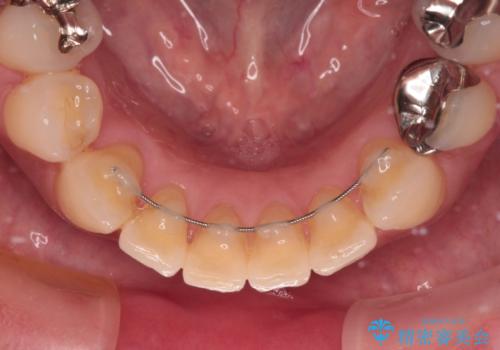

中途半端な矯正治療と前歯の欠損 再矯正とオールセラミッククラウンによる補綴治療

- 矯正治療を行ったものの、隙間やデコボコが多く、欠損している前歯も気になるとのことで来院された患者様です。

当初はセラミック治療だけを希望されていましたが、上下前歯のデコボコが顕著であったため、セラミッククラウンにて治療する前に再度矯正治療を行った方が仕上がりがきれいになると説明し、再矯正を行うこととしました。

矯正治療により前歯横幅のバランスを整えた後に、上顎前歯をオールセラミックブリッジにて補綴治療を行うこととしました。

舌突出癖により、上下前歯が突出して離開してしまったため、舌のトレーニングを徹底的に行いました。